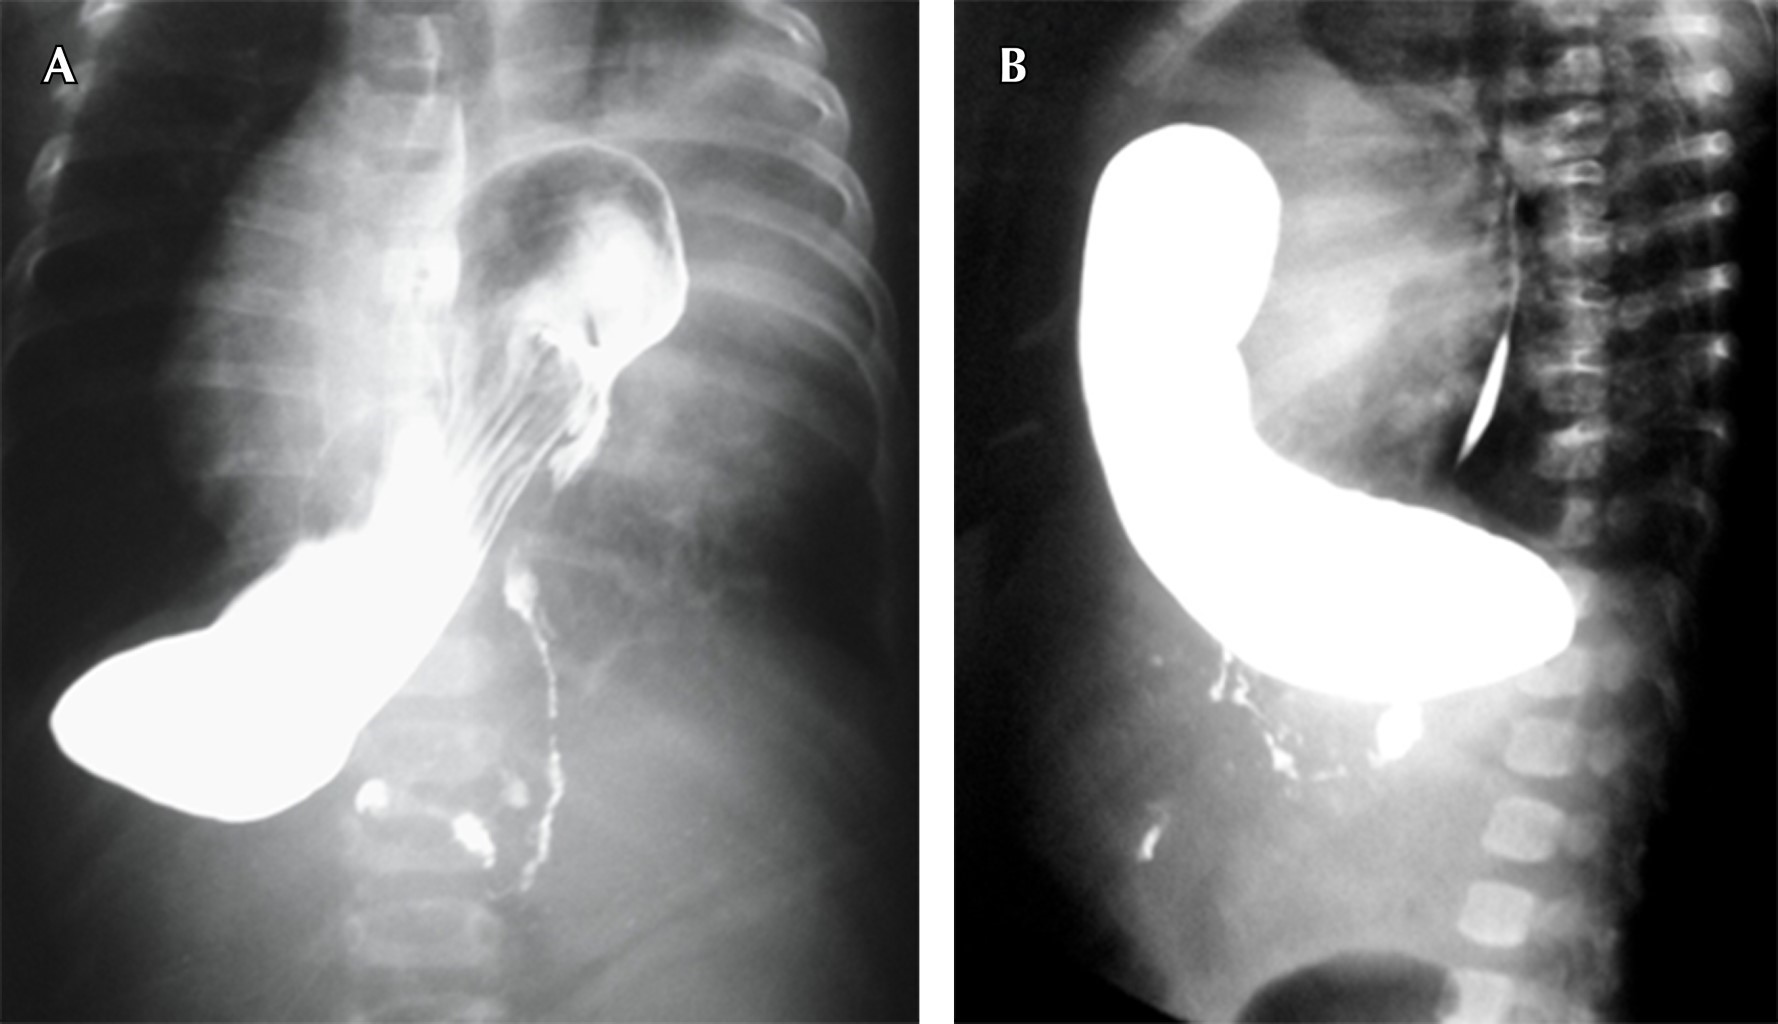

Hospitalizada en cuatro ocasiones desde los siete meses por dificultad respiratoria catalogada como neumonía de la comunidad (Figura 1A). A la exploración física: frecuencia cardiaca 162 lpm, respiración de 45 rpm, saturación: 89%. Fenotipo Down (braquicefalia, epicanto, cuello corto, puente nasal aplanado, protrusión lingual pliegue palmar), campos pulmonares con hipoventilado en hemitórax izquierdo, así como crepitantes en base pulmonar izquierda, abdomen blando depresible. Pruebas de laboratorio: TSH 48 mU/l, T4 0.5 ng/dl, radiografía de tórax revela niveles hidroaéreos, así como asa intestinal en el espacio retroesternal (Figura 1B y 1C). Medio de contraste demostrando imagen de asa intestinal en cavidad torácica (Figura 2). El Servicio de Cirugía reportó saco herniario con presencia de estómago y bazo, defecto de 4 cm de diámetro aproximadamente.

El diagnóstico de HDC se establece mediante un estudio de contraste del tracto gastrointestinal (Figura 2B).6

Figura 2